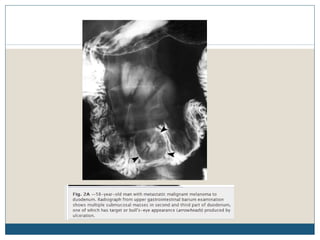

Trato gastrointestinal

 Melanoma é o tumor sólido que mais frequentemente

produz metástases para o intestino delgado.

 Isto foi ilustrado por uma série, em que 110 de 2500

pacientes (4,4 %) tiveram envolvimento GI. Destes, 35 %

apresentaram lesões no ID.

 Lesões metastáticas que envolvem o trato gastrointestinal

são geralmente múltiplas, e envolvem a borda

antimesentérica do intestino.

 A avaliação radiográfica é indicada em pacientes com

melanoma que apresentam sintomas (anemia,

sangramento evidente, dor, obstrução), ou perda de peso

inexplicável.

Trato gastrointestinal  Melanomaé o tumor sólido que mais frequentemente produz metástases para o intestino delgado.  Isto foi ilustrado por uma série, em que 110 de 2500 pacientes (4,4 %) tiveram envolvimento GI. Destes, 35 % apresentaram lesões no ID.  Lesões metastáticas que envolvem o trato gastrointestinal são geralmente múltiplas, e envolvem a borda antimesentérica do intestino.  A avaliação radiográfica é indicada em pacientes com melanoma que apresentam sintomas (anemia, sangramento evidente, dor, obstrução), ou perda de peso inexplicável.